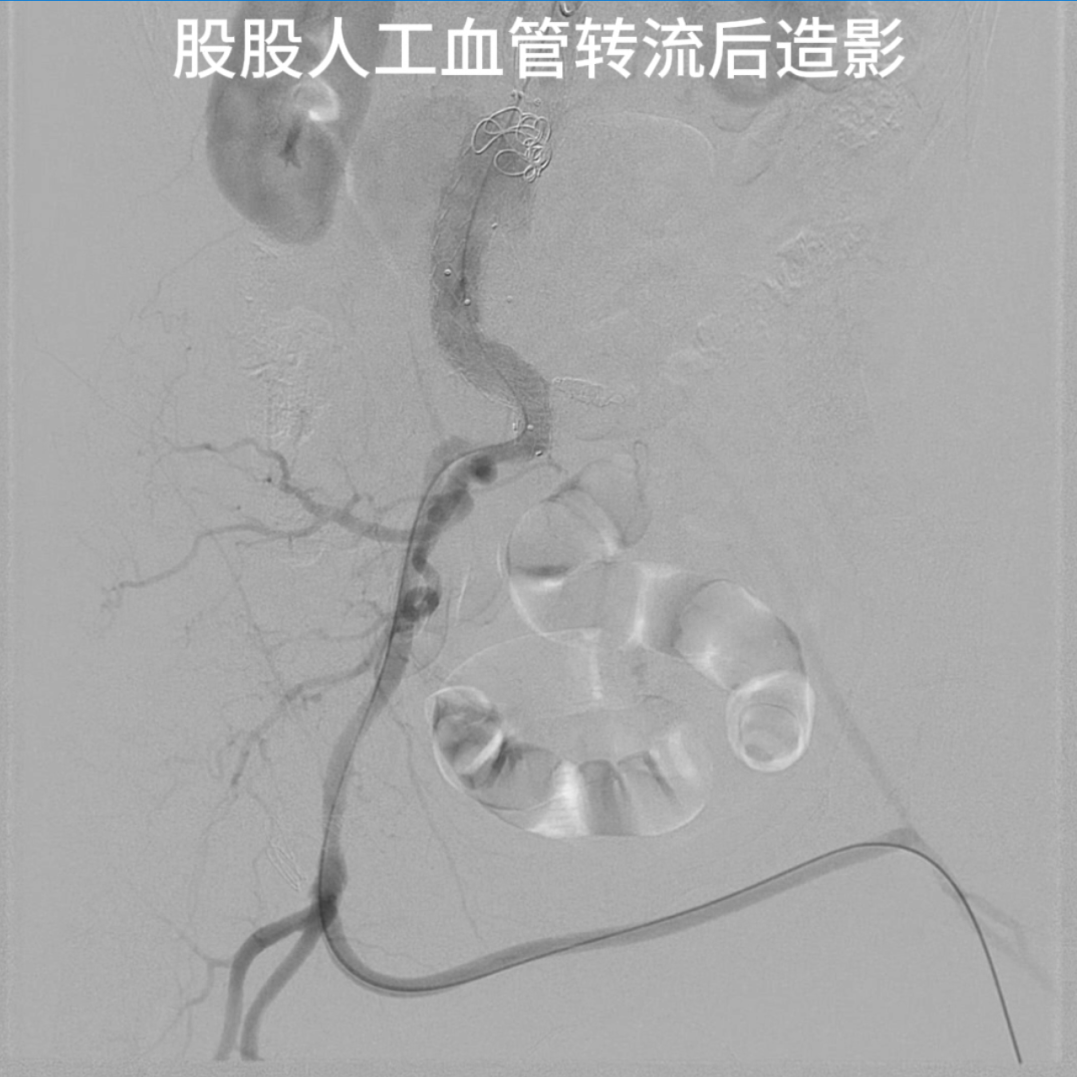

股股旁路重建

以8mm人工血管经耻骨联合皮下隧道行双侧股总动脉转流,恢复左下肢血运,造影显示人工血管桥通畅无狭窄。

6个月随访CTA显示动脉瘤完全封闭,无Ⅰ型、Ⅱ型内漏;右侧髂动脉及人工血管桥通畅,左侧髂内、外动脉显影正常。